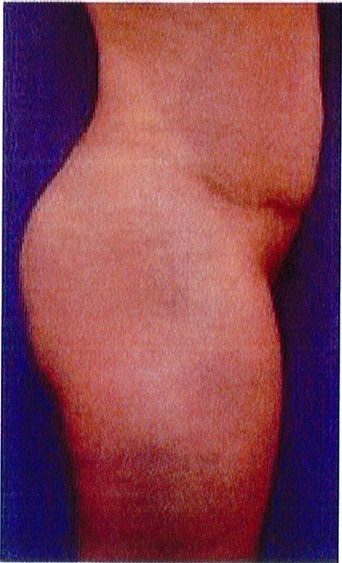

Hình. 18.. (A) Hình anh trước và (B) và sau phẫu thuật làm đầy mông của bệnh nhân được đặt khối implant dưới cân thể tích 225 mL, hai bên.

Bệnh nhân 31 tuổi tiền sử khỏe mạnh, có chỉ định nâng mông bằng implant do thiếu hụt thể tích. Hai khối anatomic implant 225 mL polyurethane dạng gel được đặt ở vị trí dưới cân. Sau phẫu thuật không ghi nhận biến chứng trong suốt quá trình hồi phục, vết mổ liền tốt (Hình 18).